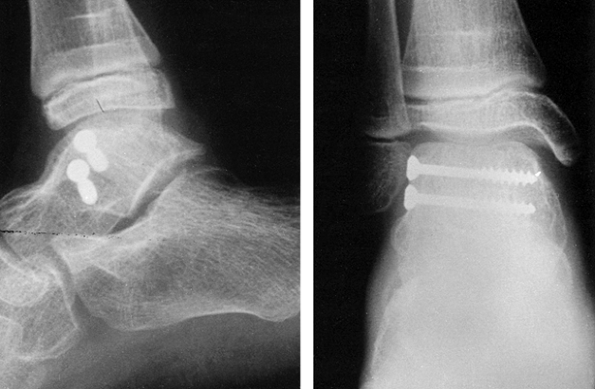

![]() |

Figure 11.24. A grade 3 open tibial fracture with bone loss in a patient with other open fractures. A: Clinical appearance on admission. B: Radiographic appearance on admission. C,D:

Stabilization of the fracture with two-plane bilateral pin configuration proximally and three anterior pins distally. Bone graft had been delayed for 3 months because of adult respiratory distress syndrome. E: At 8 months, after the patient had started full weight bearing, the frame was gradually reduced. As a last step before removal, the proximal pin was loosened. F: Radiographs 1 year after injury. |